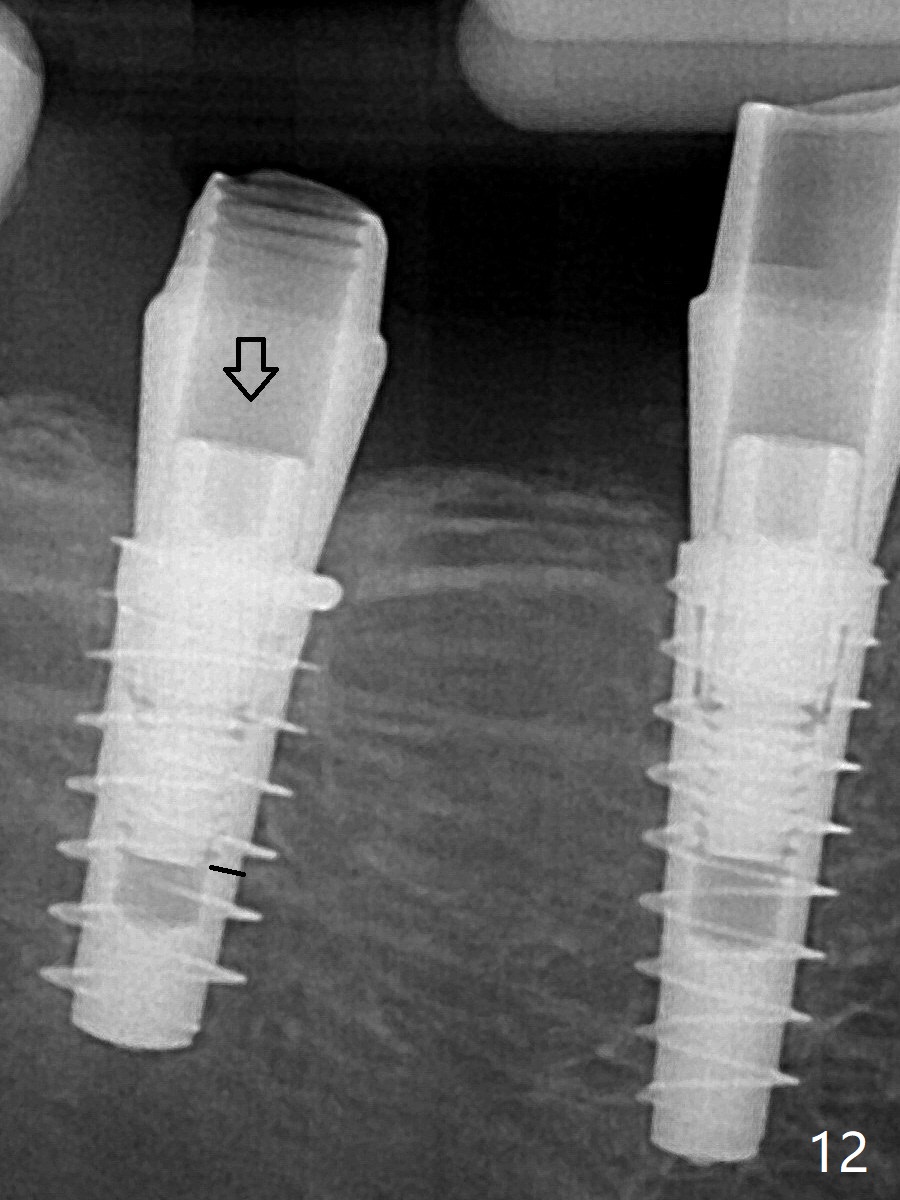

改用5.5x4(5)毫米UF(不同品牌)基台,临床上不能就位,局麻使用5.5毫米Profile Drill后,才能就位(图十三),螺丝下端超越最低螺沟(横线)。